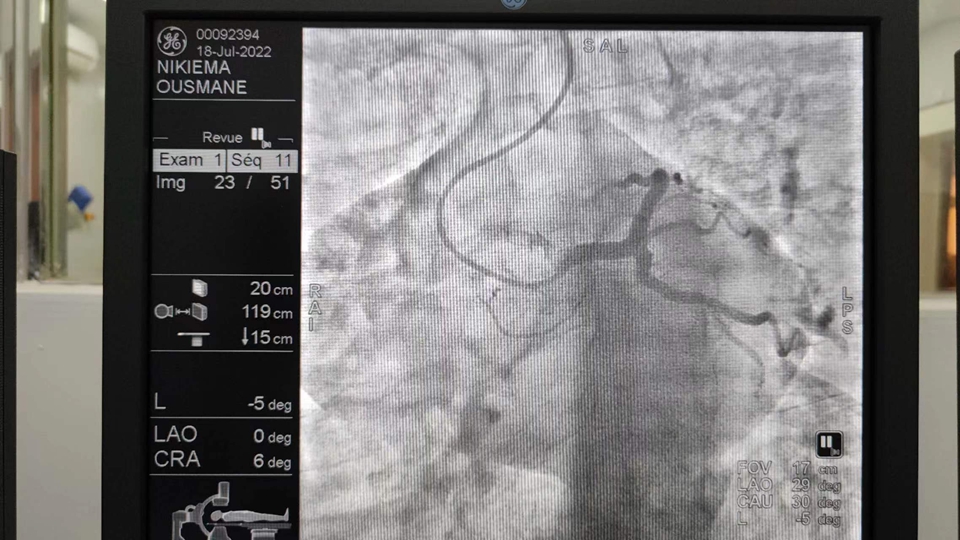

7月15日,我在门诊接诊了一名50岁的男性患者,因“反复胸闷3月”来医院就诊,患者有糖尿病和肺部疾病,当地Hippolyte SOME医生讨论病情后,考虑患者为冠心病,决定为患者施行冠状动脉造影术。

7月18日上午9点,我们为患者施行冠状动脉造影术检查,术中造影显示:患者心脏右冠管壁不光滑,左冠脉正常。经分析研判后,诊断为“冠状动脉粥样硬化”。9:40左右,手术顺利完成。

不同国籍、不同肤色的医护人员,团结一心,共同完成了这例非洲的心脏手术,得到了当地医生同行的好评。当天共完成两台冠脉造影手术。